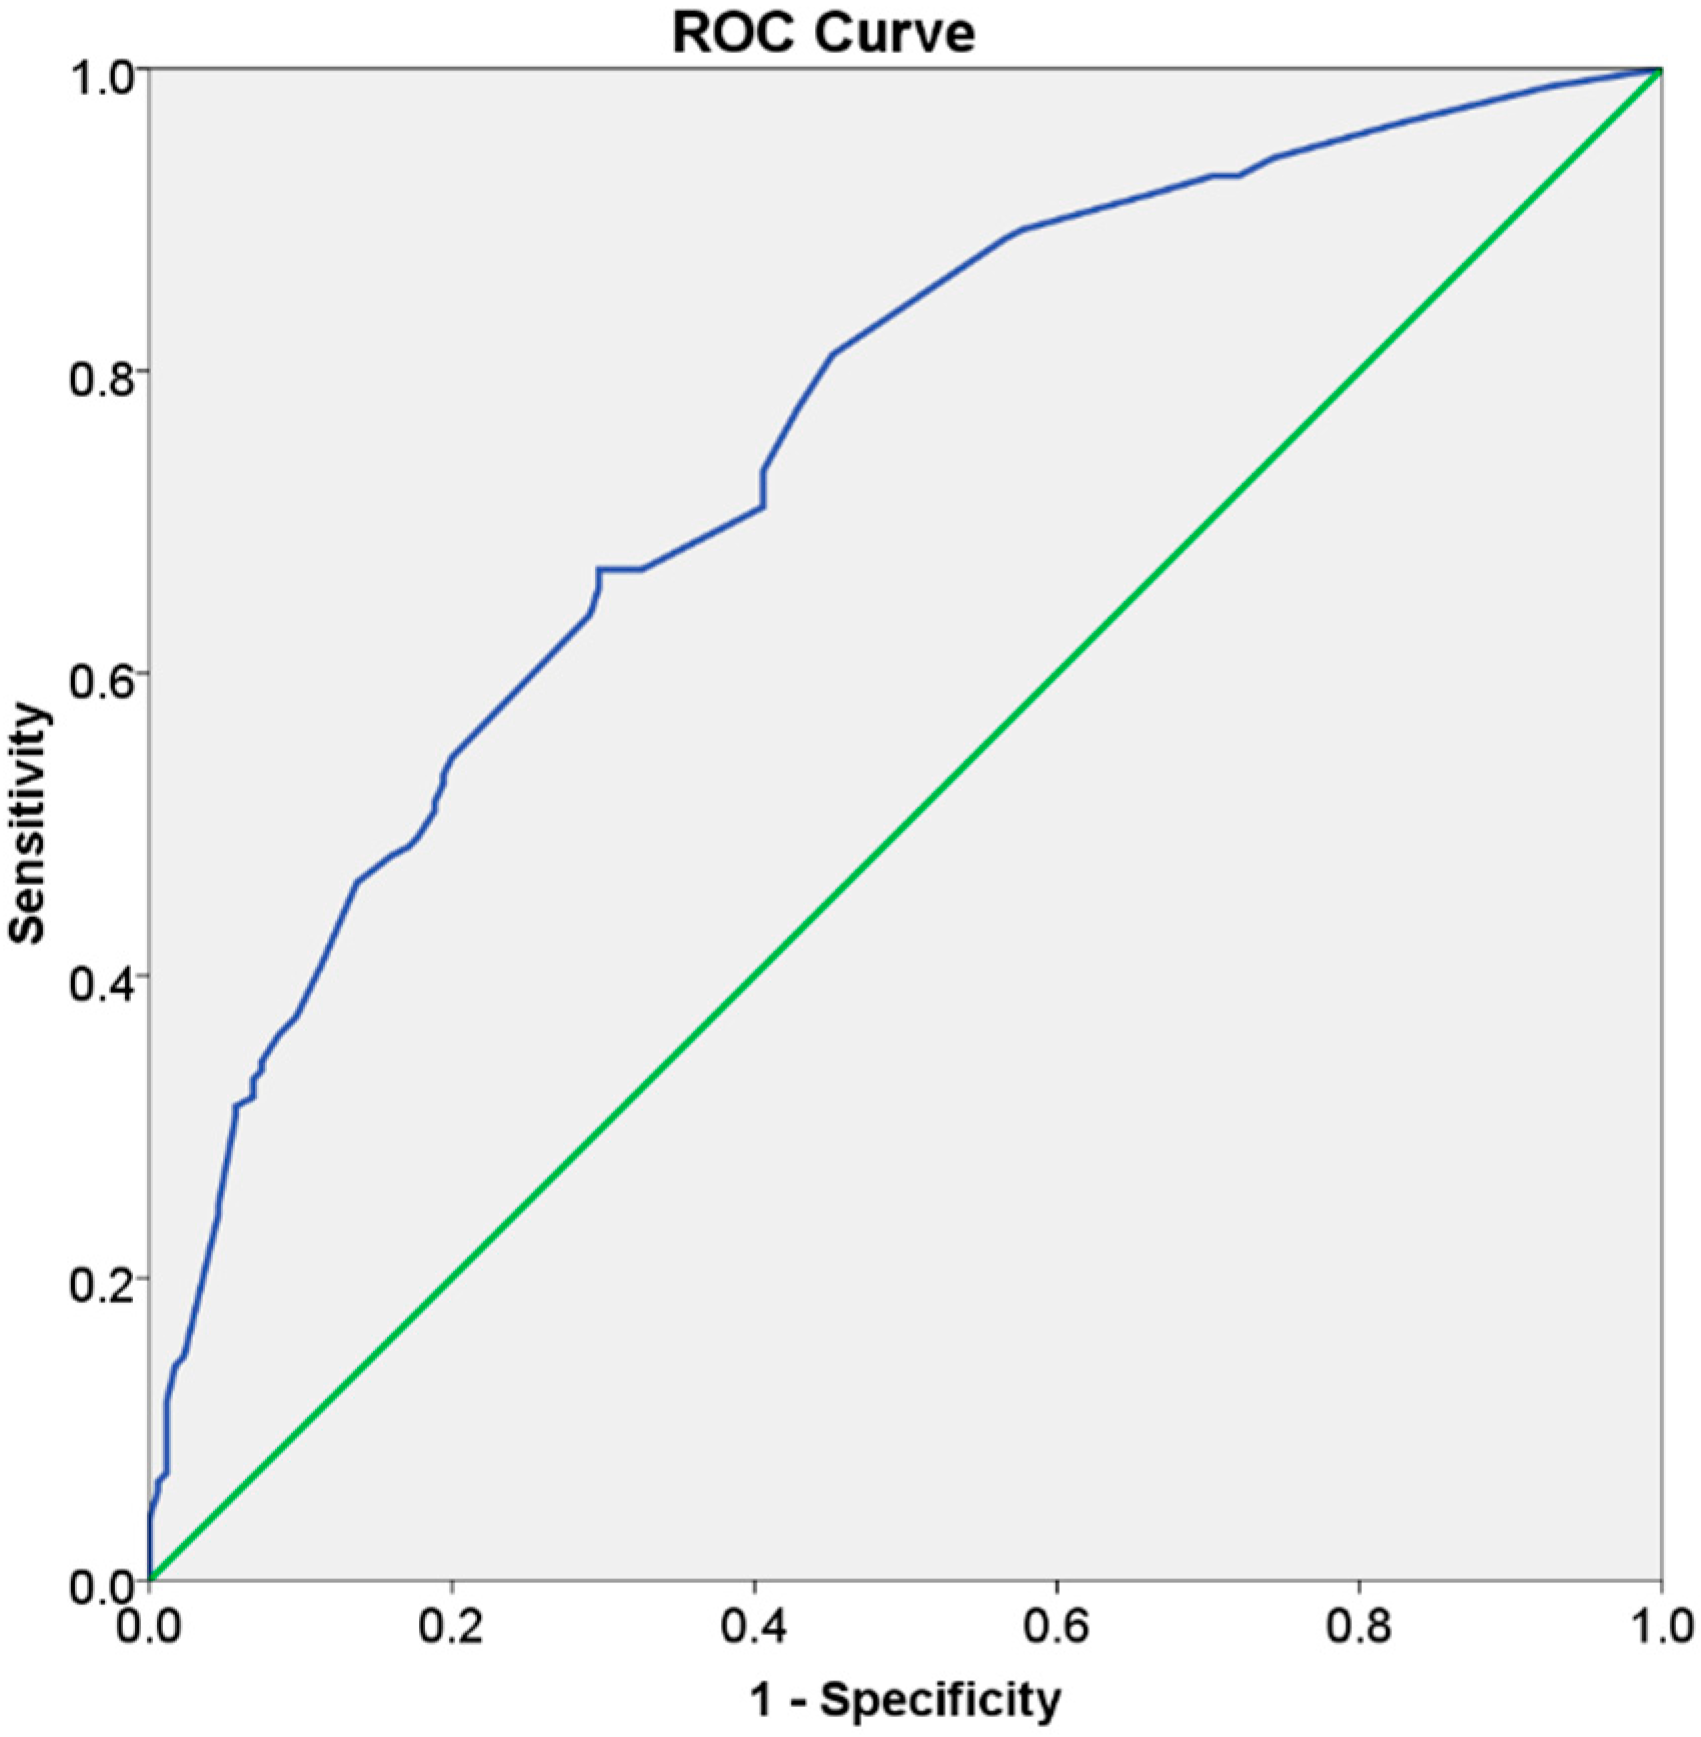

3.3. Risk Score

| C-statistic (95% confidence interval) = 0.75 (0.70; 0.80); p < 0.001 | |||